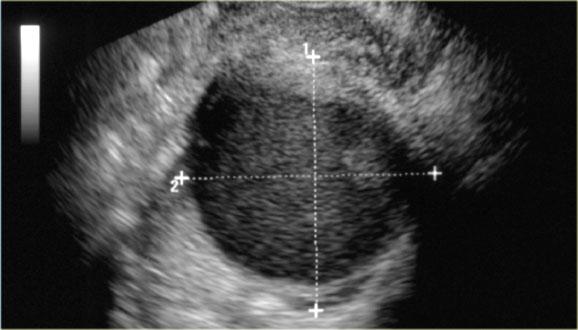

Các hình ảnh siêu âm qua ngã âm đạo cho thấy một nang buồng trứng phức tạp nhỏ với mạch máu thành nang trên phân tích Doppler năng lượng.

Hình ảnh Doppler vòng tròn đặc trưng này được gọi là dấu hiệu ‘vòng lửa’ (ring of fire).

Lưu ý, có hiện tượng xuyên âm tốt và không có mạch máu bên trong, phù hợp với nang hoàng thể đang thoái triển một phần.

Một trường hợp khác với hình ảnh điển hình của dấu hiệu ‘vòng lửa’ trên siêu âm.

Nang hoàng thể trên MRI: hình ảnh chuỗi xung T2W mặt cắt ngang cho thấy nang hoàng thể đang thoái triển (mũi tên).

Đây là hình ảnh bình thường.

Buồng trứng phải cũng bình thường.